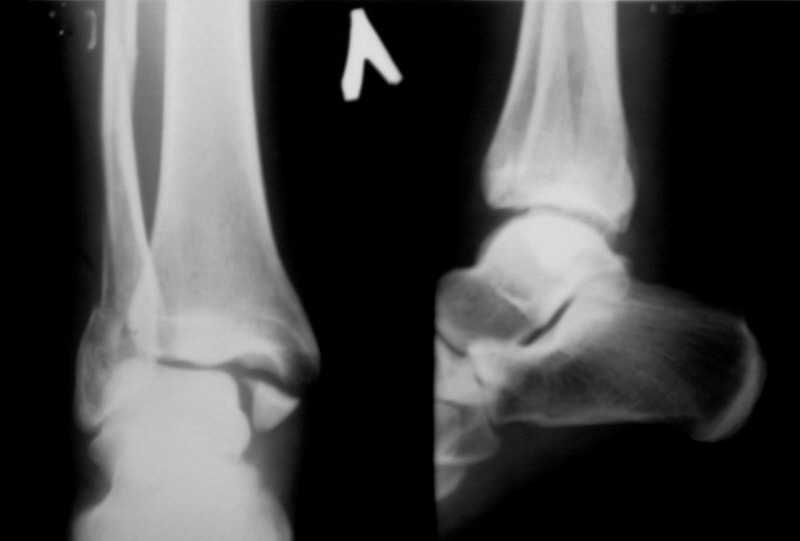

Вот рентгенконтроль на 7-е сутки после репозиции.

Стандартными снимками считается прямая, боковая и мортиз!!!, а так трудно гадать, насколько потеря длины малоберцовой. На боковом снимке не сопоставленный перелом медиальной лодыжки и перелом заднего края без смещения.

In this case we say about three malleolar fracture of ankle.Moreover lateral malleolus have external rotation displacement.Becouse this great suprise to me question - what kind of treatment.Of course open reduction with internal

fixation.

Ув. коллеги. Мы считаем, что синтезировать необходимо медиальную лодыжку, она ротирована. Малоберцовую кость лучше не трогать. Довольно травматично будет, фрагменты неплохо стоят. И то, оперировать медиальную лодыжку где-то в трехнедельном сроке, чтобы малоберцовую кость не развалить. Мнений много, мы благодарны за участие.

Очень жаль, что Вы так считаете и не прислушались к мнениям уважаемых коллег. Проблема этого голеностопного сустава не в "висячей" внутренней лодыжки, а ротированной и, возможно, укороченной малоберцовой кости. На снимках подвывиха как-буд-то бы нет, но таран ротирован и это в дольнейшем будет причиной раннего артроза.